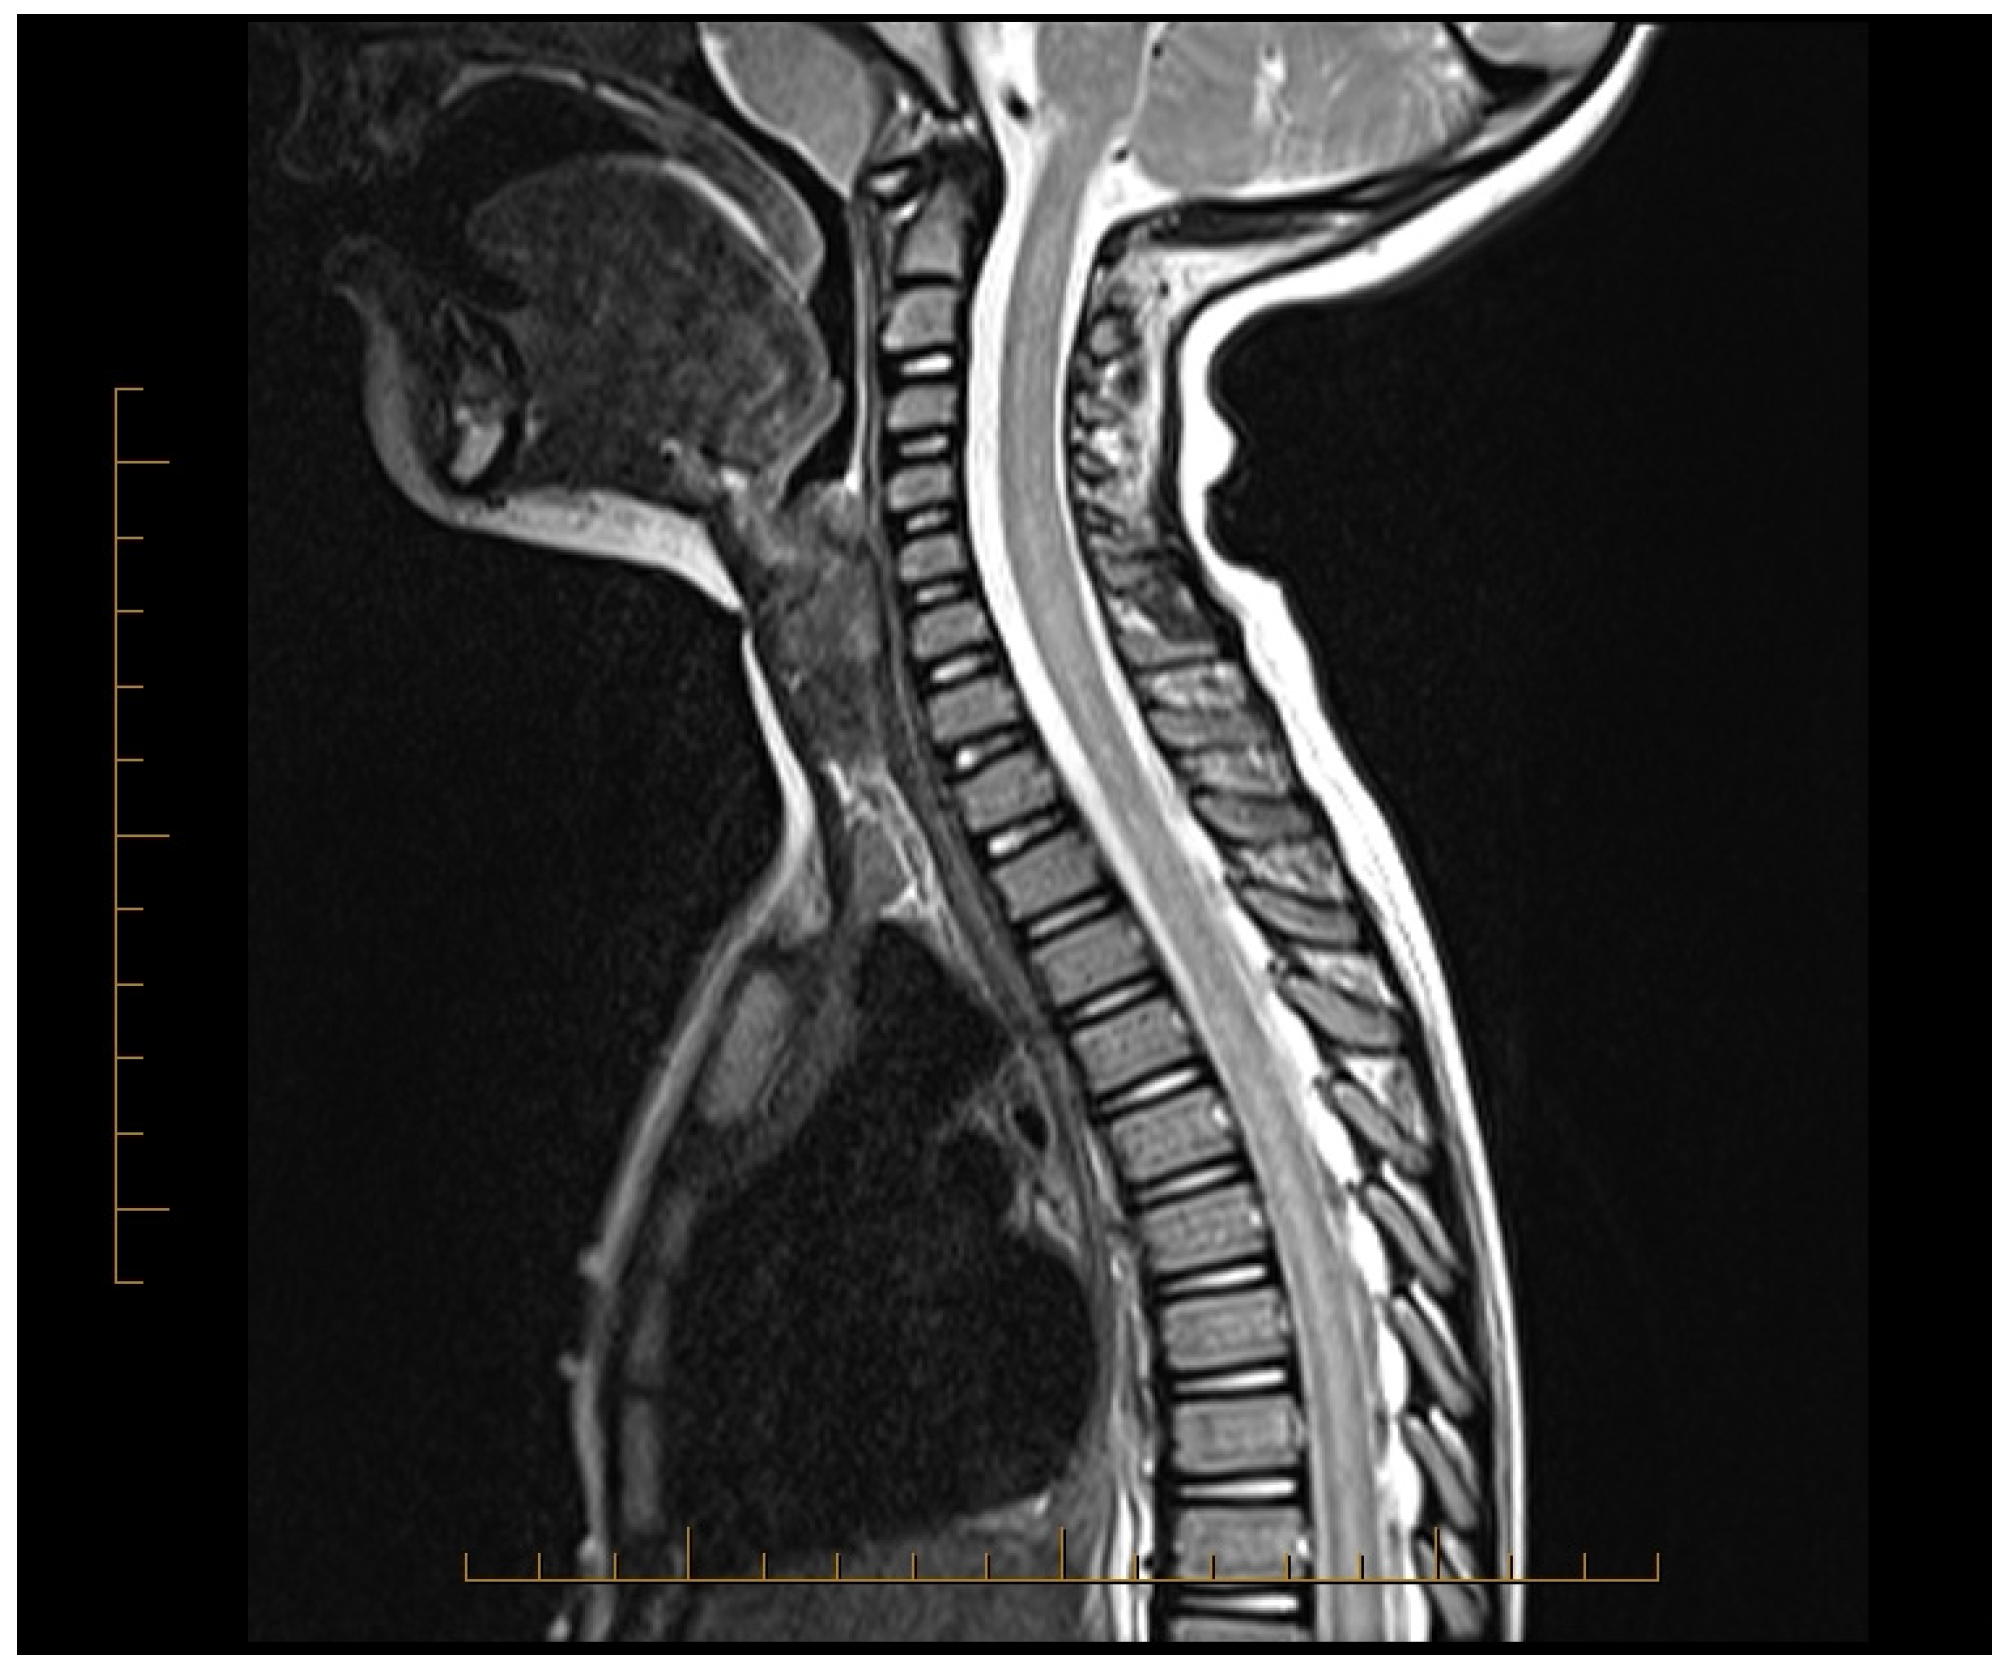

| 2017 | Hsu [27] | CR | Taipei, Taiwan | 1 | 12 | M | Sudden onset low back pain followed by quadriplegia, hyperalgesia, flaccid bladder, and altered consciousness. MRI showed diffuse T2 hyperintensity from cervical cord to conus medullaris. | MP TPE | After TPE, limb function improved, bladder/rectal issues resolved. At 6 months: independent eating, supported ambulation, EDSS 5 |